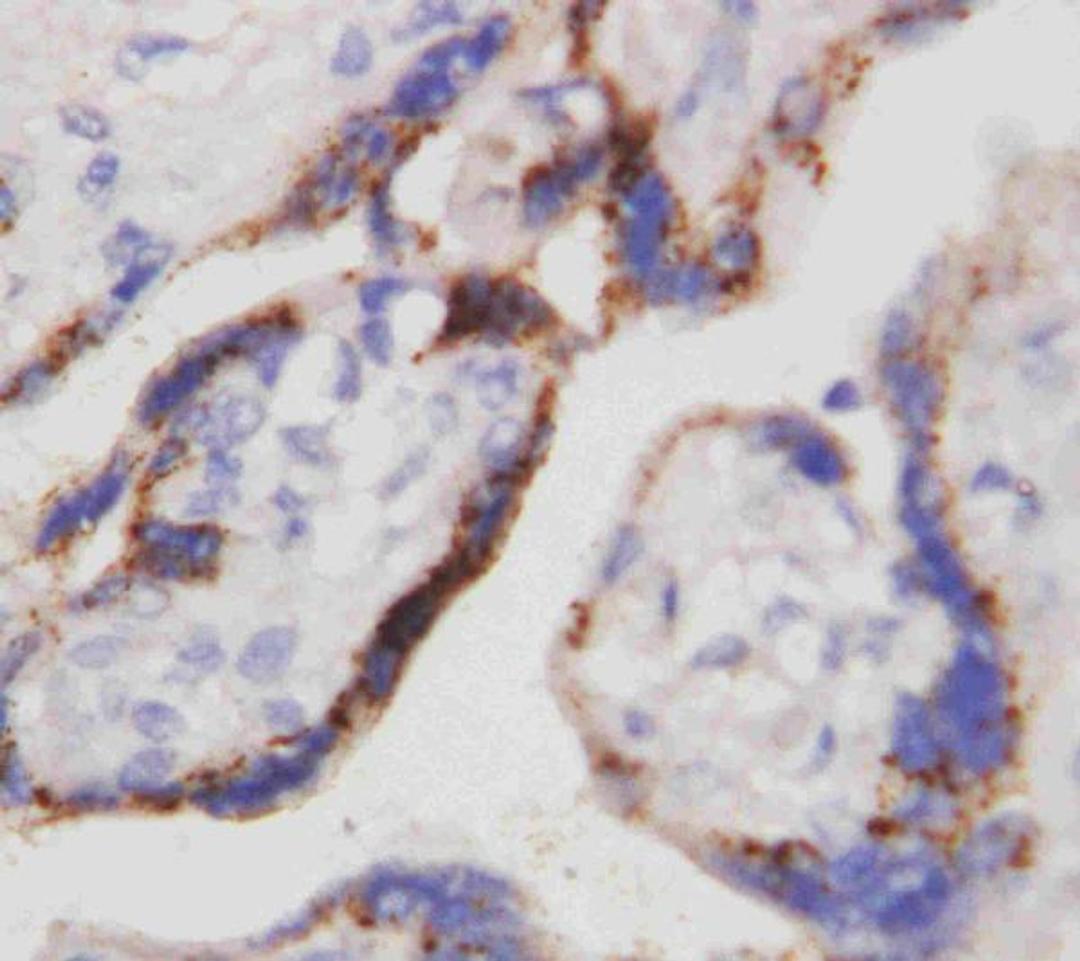

Boster Bio Anti-Beta-HCG CGB Antibody (Monoclonal, PC-2) catalog # MA1111. Tested in IHC applications. This antibody reacts with Human.